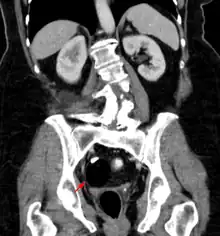

| A small (4 cm) dermoid cyst of an ovary, discovered during Cesarean section | |